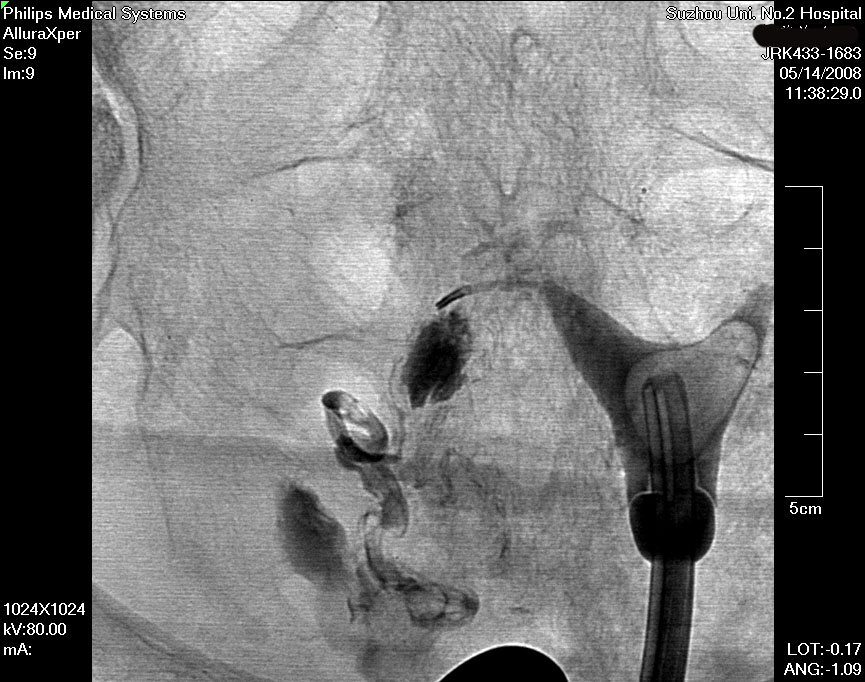

在清晰的DSA(数字减影血管造影机)的同步监测,采用同轴导管系统,进行输卵管选择性造影和再通术,主要适用于输卵管阻塞于间质部及狭部的不孕症患者,各段输卵管阻塞均可行选择性输卵管造影、通液。主要采用导管扩张术,插入导管导丝,利用导管导丝的推进扩张分离作用和造影剂的冲击力等,使输卵管疏通至伞端。手术安全高效,痛苦小,无需住院,复通率及术后妊娠率均较高。(见图1术前HSG宫腔形态正常,双侧输卵管不显影、图2左侧输卵管顺利通过导丝后造影剂通过畅、图3右侧输卵管通过导丝后畅)